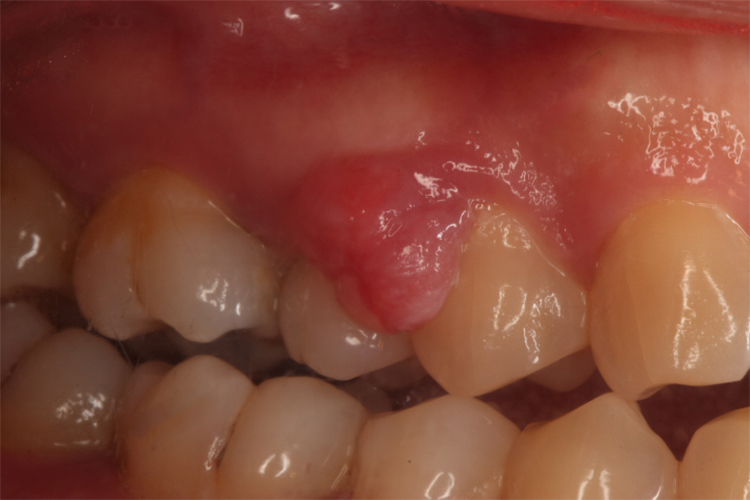

最常见的部位是前磨牙区,肿块较局限,呈圆形或椭圆形,有时呈分叶状。大小不一,直径数毫米至数厘米。有蒂者呈息肉状,无蒂者基底宽广。较大的肿块可遮盖部分牙及牙槽突,表面呈红色或暗红色,质地一般较软,触时易出血。